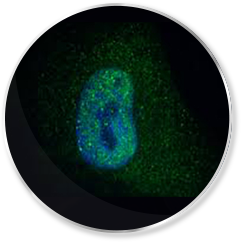

Immunofluorescence

Fluorescently-labelled antibodies specific to CTCs and leukocytes can be used to identify and enumerate CTCs or detect cancer-specific biomarkers.